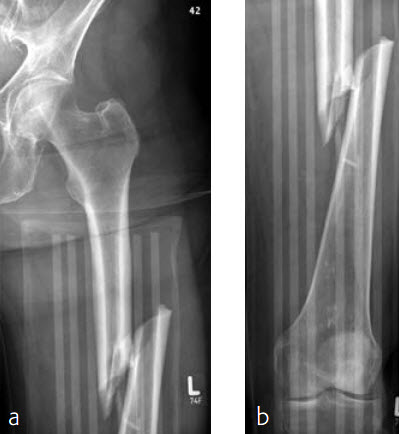

Case 2: Left femur fracture

A 70-year-old female patient suffered an AO 32-B3 fracture of the left femur (Figs 3 and 4). Fixation with the FRN for a tip of the trochanter entry point (nail diameter 10 mm; nail length 400 mm; reaming to 12 mm) in standard interlocking mode (Figs 5 and 6). Proximal locking with antegrade and transverse dynamic locking positions. Distal locking with two lateral to medial locking screws in static locking position.